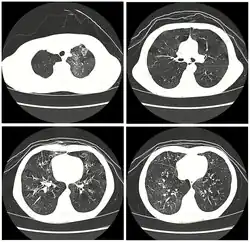

| High resolution CT scan showing bronchiolitis obliterans with mosaic attenuation, bronchiectasis, air trapping and bronchial thickening[3] | |

Early in the disease chest radiography is typically normal but may show hyperinflation.[6] As the disease progresses a reticular pattern with thickening of airway walls may be present.[4][6] HRCT can also show air trapping when the person being scanned breathes out completely; it can also show thickening in the airway and haziness in the lungs.[11] A common finding on HRCT is patchy areas of decreased lung density, signifying reduced vascular caliber and air trapping. This pattern is often described as a "mosaic pattern", and may indicate bronchiolitis obliterans.[6]